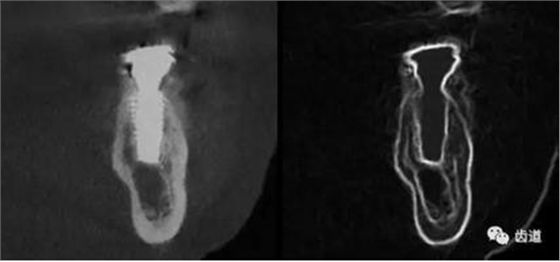

CBCT在牙體牙髓病科治療中,對(duì)牙根周圍的解剖關(guān)系、炎癥病變、囊腫等就能夠輕而易舉的進(jìn)行診斷。甚至與牙齒內(nèi)根管的數(shù)目、走向、分支等都能夠通過(guò)牙科CT進(jìn)行展示,使臨床醫(yī)生的根管治療不再是完全憑手感的“經(jīng)驗(yàn)科學(xué)”。通過(guò)CBCT,還可以對(duì)一些“久治不愈“的疑難病例進(jìn)行檢查和診斷,例如根縱列的診斷、根管內(nèi)異物的定位等,找準(zhǔn)了原因,結(jié)合先進(jìn)的治療技術(shù)因病施治,使疑難病例的治療變的輕松起來(lái)。

1、牙髓根管治療

1)根管治療中牙膠尖充填在CBCT中的影像

2)根管測(cè)量